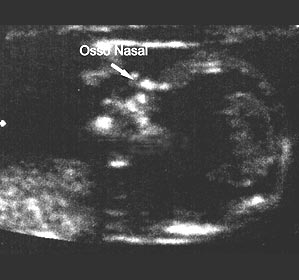

Nessa semana seu médico vai pedir um ultrassom para medição da translucência nucal. Este é um exame importante que serve para afastar, em 85%, os casos de cromossomopatias, ou seja, ele detecta má formação e anomalias causadas por alterações, tanto nas estruturas, quanto no número de cromossomos, como a Síndrome de Down. O exame pode ser feito até o final da 13º semana. Procure caminhar e ocupar-se com atividades prazeirosas, porque nesse período você pode sentir-se mais amedrontada e preocupada com seu bebê.

Essa é uma fase que, normalmente, é muito tranquila para a mãe. Pelo ultrassom já é possível saber o sexo do bebê e ver que ele está sempre se movimentando, ainda que isso ainda não seja perceptível por você.

Com um exame de ultrassom 3D é possível ter até uma noção do rosto do bebê. Se optar por esse tipo de exame de imagem, prepare-se para a primeira foto do seu filho!”

Com um exame de ultrassom 3D é possível ter uma noção do rosto. Se optar por esse tipo de exame de imagem, prepare-se para a emoção da primeira foto do seu bebê!!

Um novo exame ultrassonográfico pode ser solicitado nesta fase para avaliação do crescimento fetal, determinação do peso estimado, avaliação da quantidade de líquido amniótico, inserção da placenta, circulação sanguínea, útero-placentária e feto-placentária, e posição fetal.